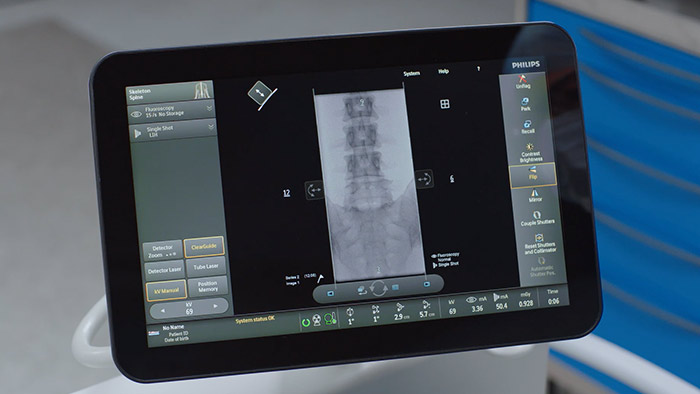

Touch screen module (TSM)

As an addition to the Zenition 70 platform, the Touch screen module2 (TSM) supports table-side control for surgeons during procedures. Via the touchscreen, you can select, drag and zoom items with ease. This means you can view images instantly, giving you greater image control during procedures.